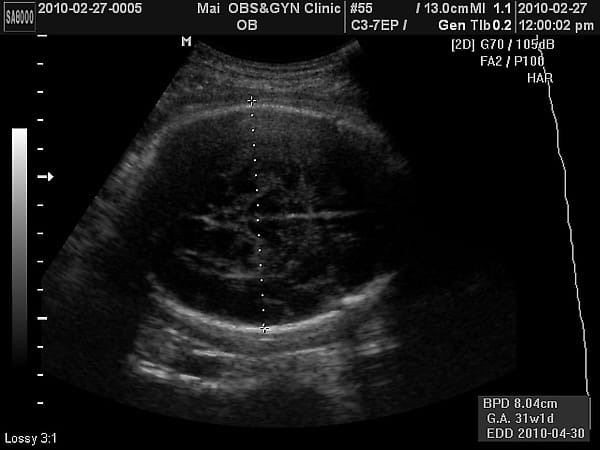

頭直徑8cm,31周左右的尺寸。醫生說:頭小了點,這是遺傳。

大腿和其他部分都是34-35周左右,屬於正常範圍。